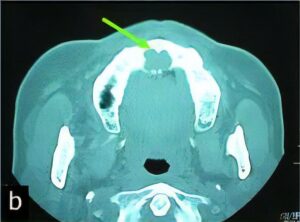

のう胞

のう胞は、何らかの理由で“水を含んだふくろ”ができてしまう病気です。特に顎骨は、のう胞ができやすいと言われています。

顎骨ののう胞では、虫歯から発生する「歯根嚢胞」が大半を占めていますが、くちびるにできる「粘液嚢胞(唾液が貯まった嚢胞)」や「含歯性嚢胞(埋伏歯にできる)」など様々な種類があります。

当科ではCT、MRI、病理組織診(良性悪性の確認検査)などの検査・診断、および治療(手術)を行っています。